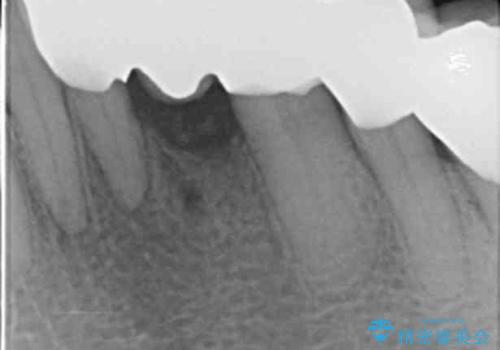

精査したところ、前歯の咬み合わせが反対になっていること、下の奥歯(下顎両側67)が4本欠損していることから動揺が生じていました。

入れ歯も抵抗があるとのことから、相談を重ね、今の状態では保存不可能な下の前歯(左下2)を抜去し、ブリッジや連結補綴により動揺を抑えることにしました。

下顎大臼歯が欠損したままで今ある歯に負担がかかりやすいことから、長期的予後は保証できないことをご理解頂いた上で治療を行いました。

気にされていた前歯と奥歯の動揺がなくなったことと自然な仕上がりに喜んで頂けました。